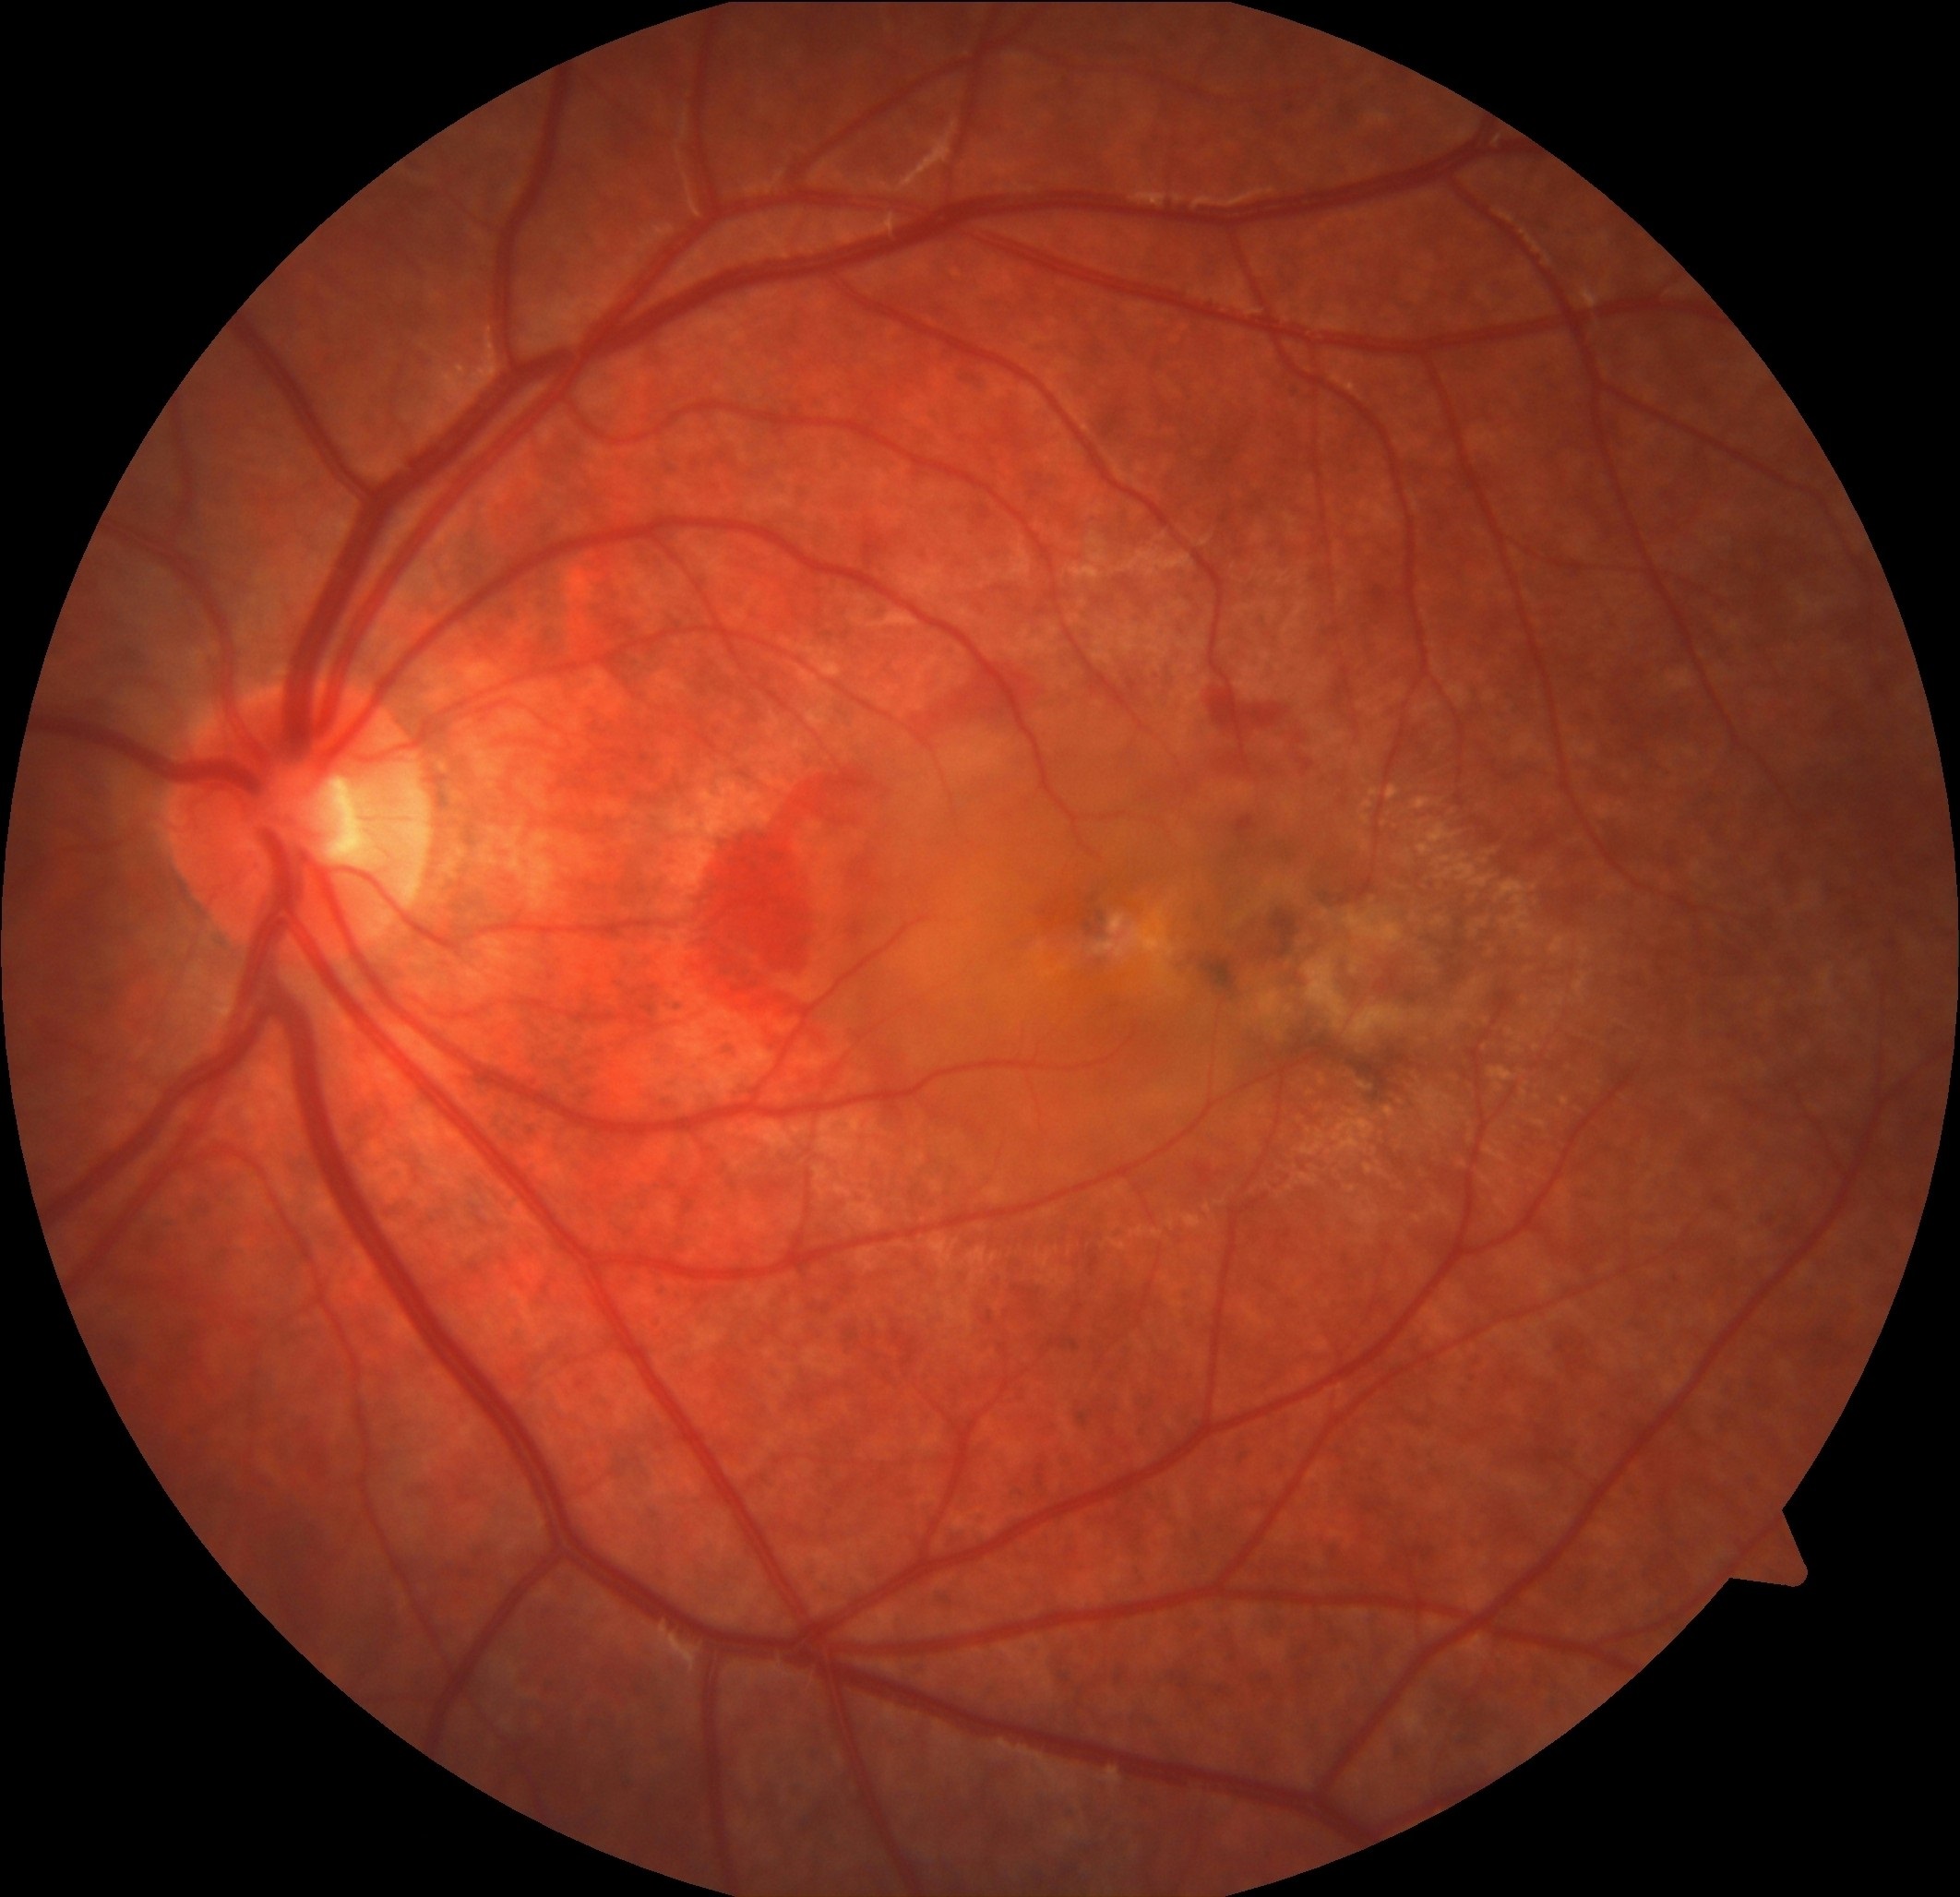

Neovasküler Yaşa Bağlı Maküla Dejenerasyonu ve Antitrombotik Tedavi

Devamı